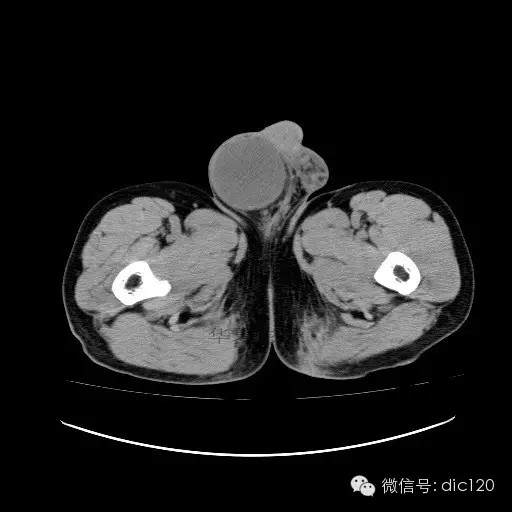

【影像表现】

青年男性,右侧睾丸肿大,边界清晰,增强后睾丸不均匀中度强化,内可见多灶囊变坏死区,动脉期肿块内有细小动脉血管显示,延迟期可见分隔样强化,鞘膜囊可见积液。

定位定性:右侧睾丸恶性肿瘤。

【影像诊断】

右侧睾丸精原细胞瘤,右侧睾丸鞘膜积液。